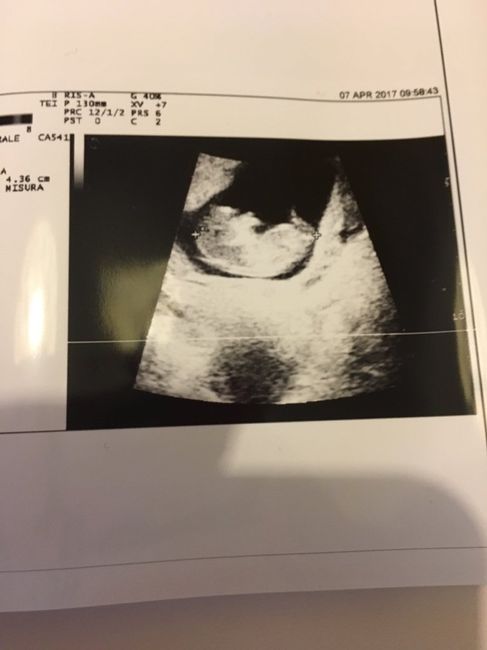

Fagiolino continua a crescere *.*

Da Arianna , Il 7 Aprile 2017 alle 11:27

Ciao ragazze,Oggi sono a 11+2 settimane, e ho fatto un controllo visto avevo un distacco di 18x10 mm da inizio gravidanza e oggi finalmente è scomparso, ho una gioia nel...